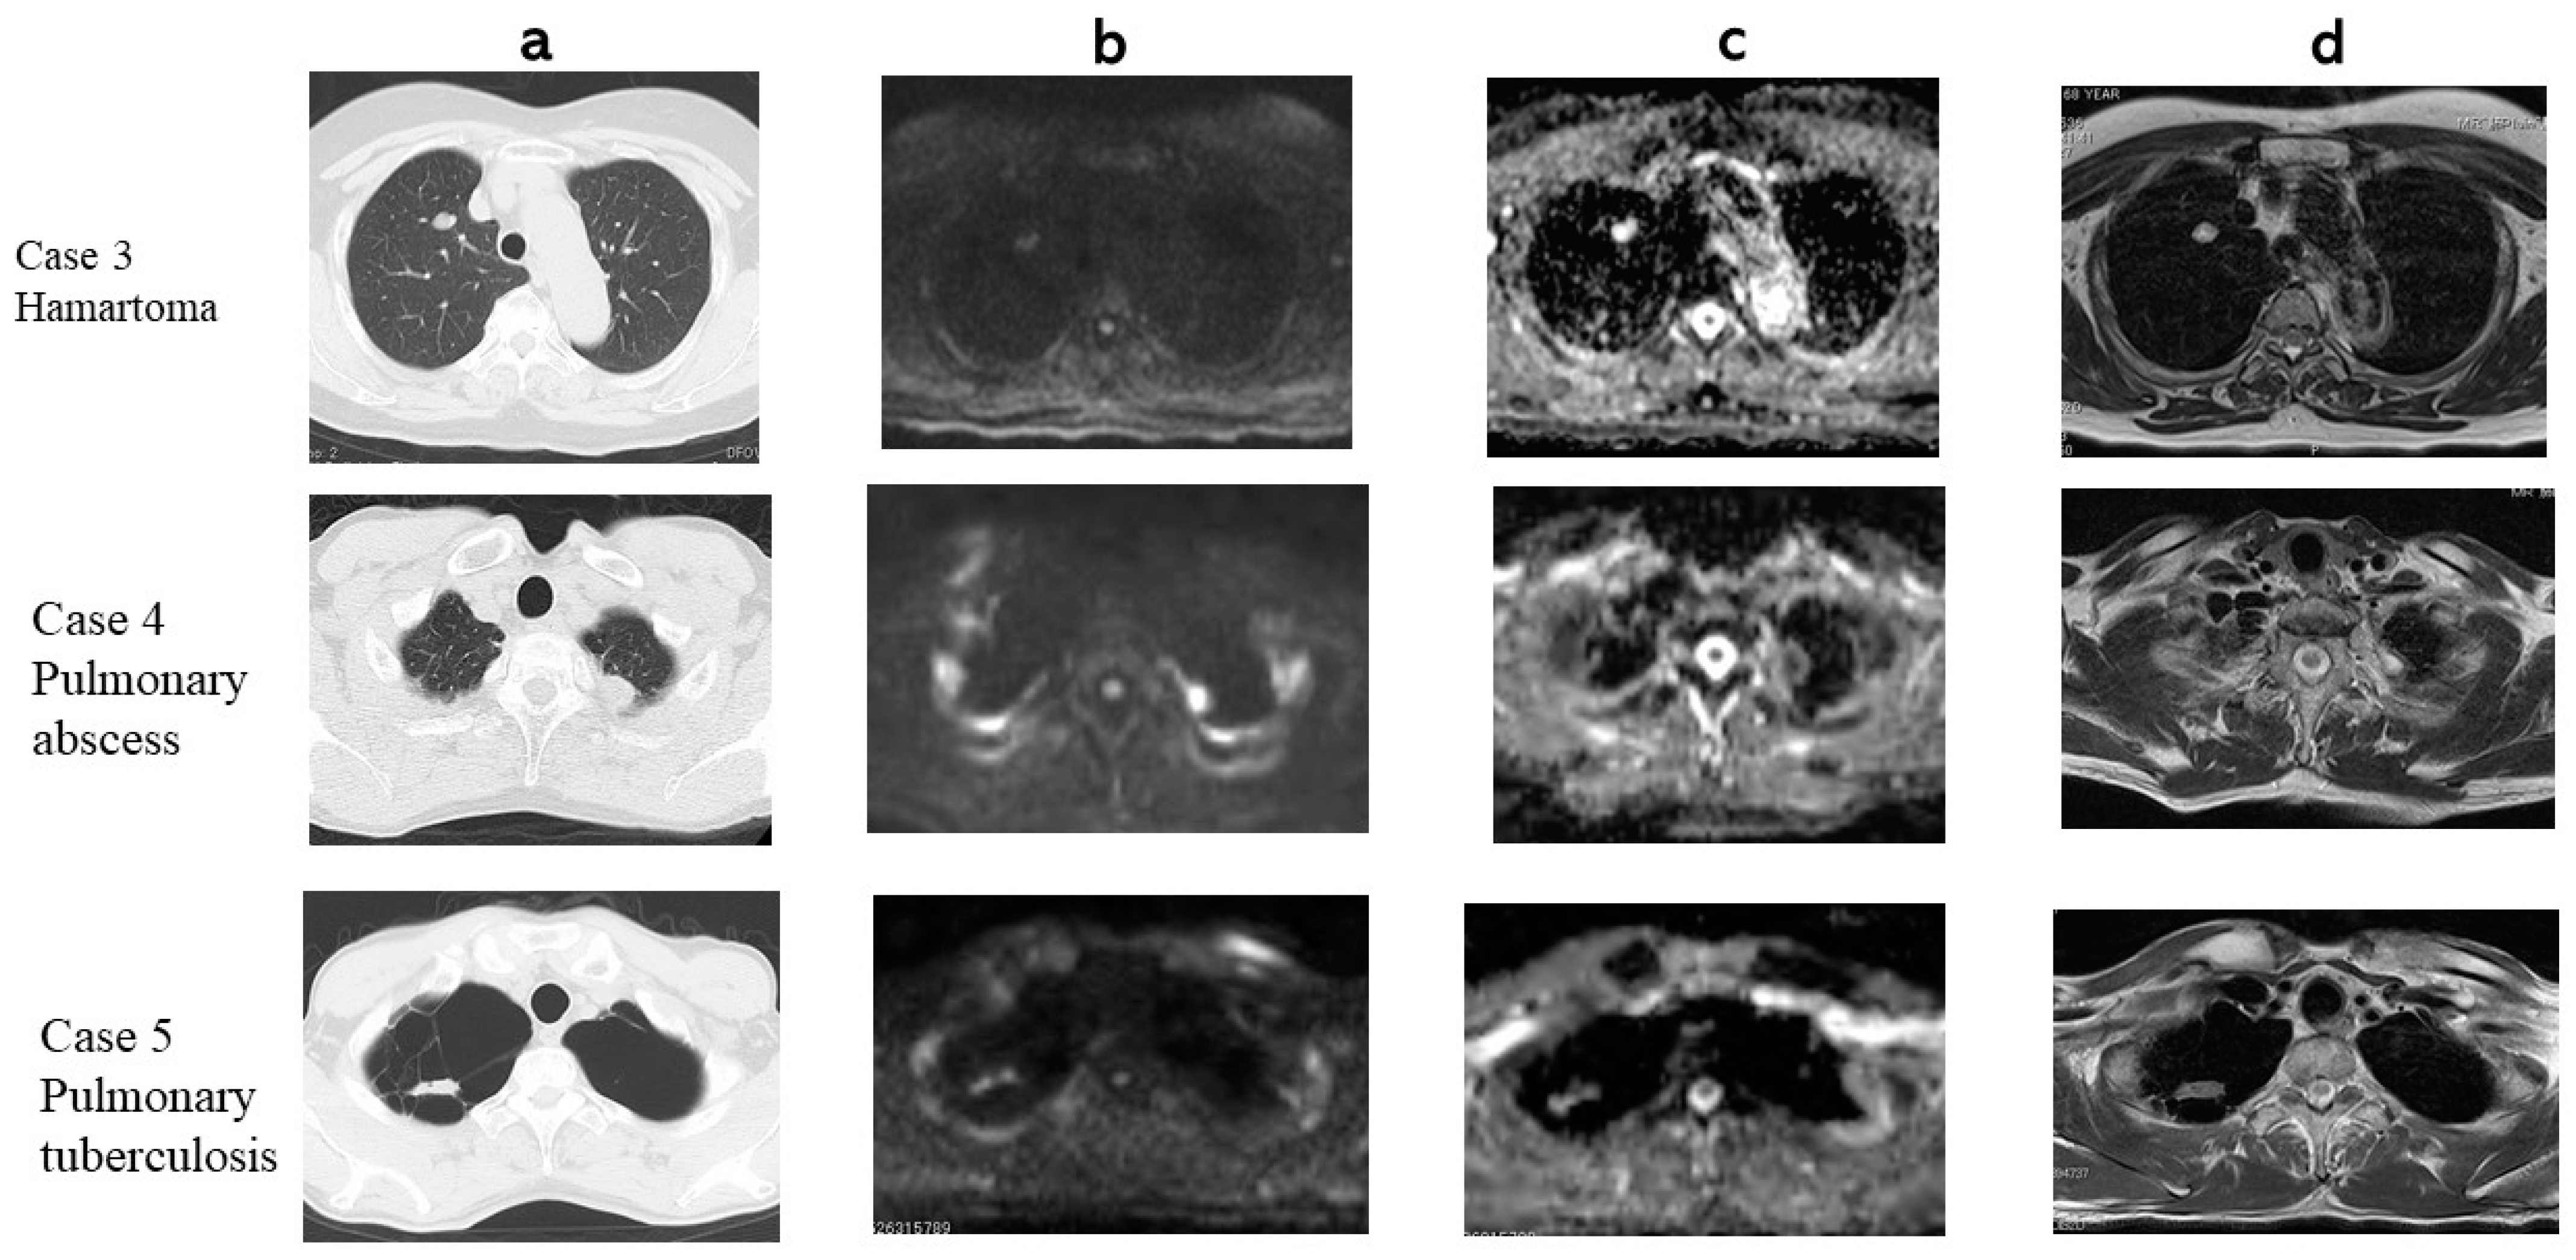

3. Results